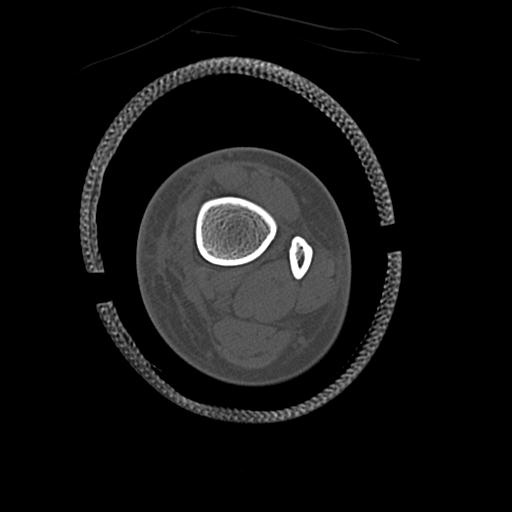

100612 11/25 1/20 右膝 2R 84歳女性 右TKA